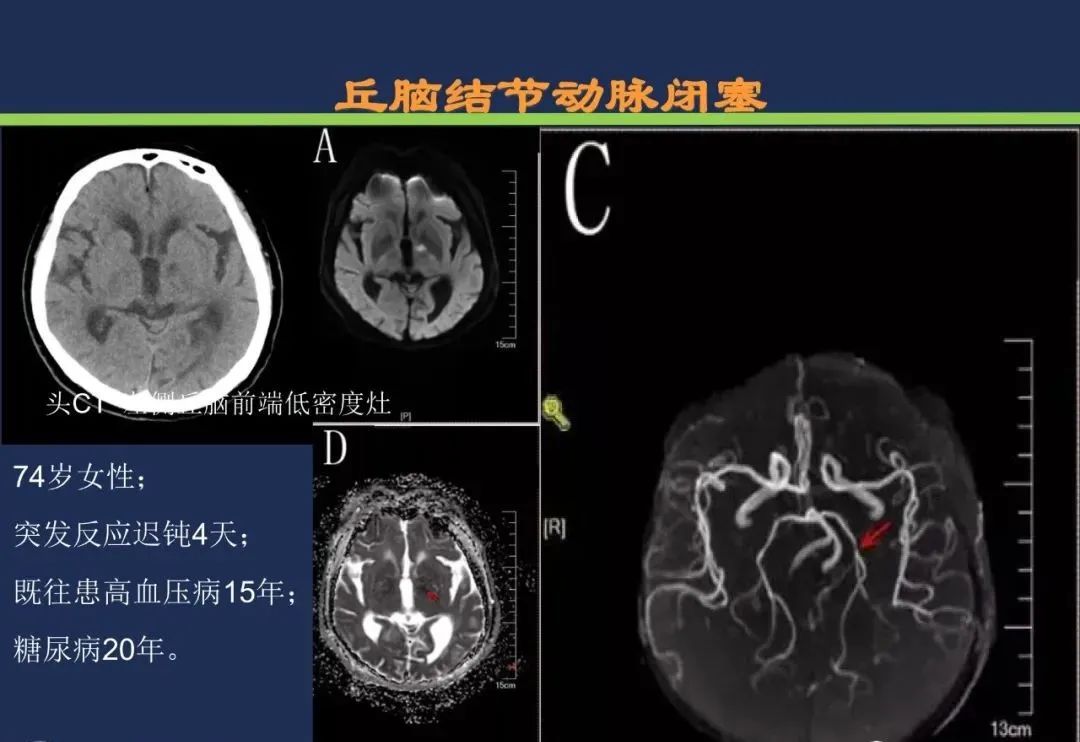

丘脑结节动脉